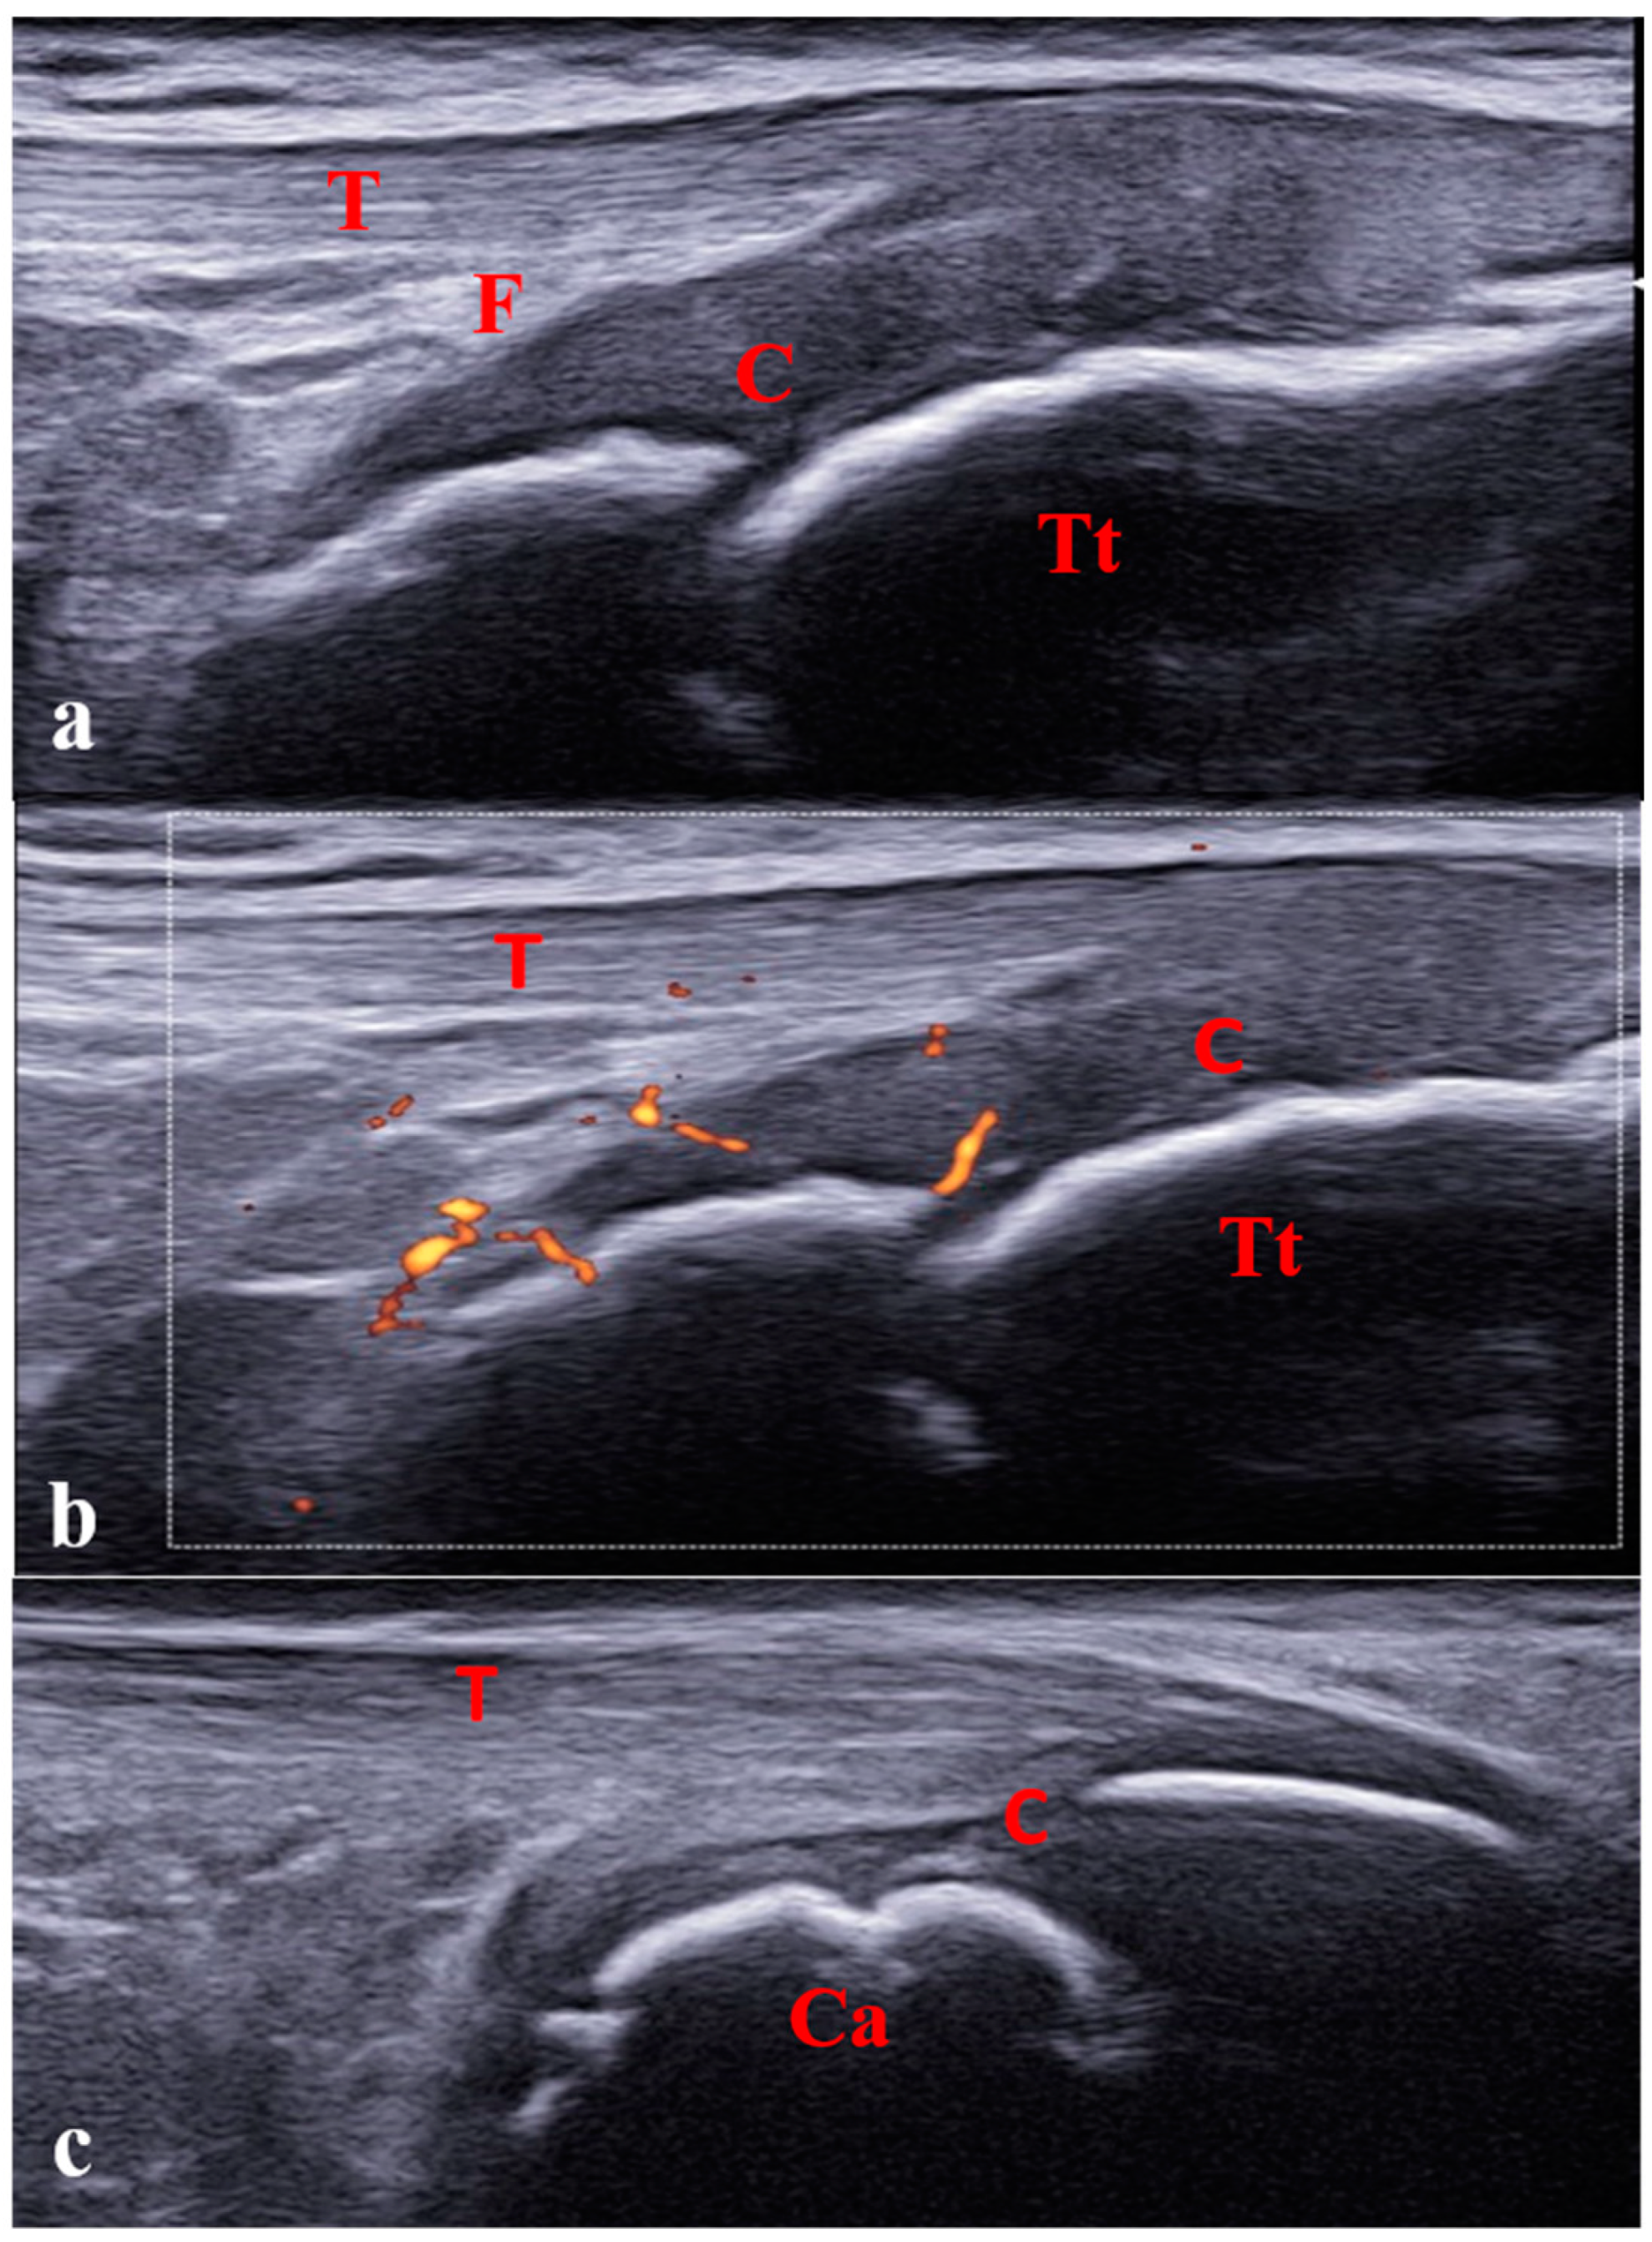

- Della Paolera, S.; Pastore, S.; Zabotti, A.; Tommasini, A.; Taddio, A. Ultrasonographic Assessment for Tenosynovitis in Juvenile Idiopathic Arthritis with Ankle Involvement: Diagnostic and Therapeutic Significance. Children 2022, 9, 509. [Google Scholar] [CrossRef] [PubMed]

- Laurell, L.; Court-Payen, M.; Nielsen, S.; Zak, M.; Boesen, M.; Fasth, A. Ultrasonography and Color Doppler in Juvenile Idiopathic Arthritis: Diagnosis and Follow-up of Ultrasound-Guided Steroid Injection in the Ankle Region. A Descriptive Interventional Study. Pediatr. Rheumatol. Online J. 2011, 9, 4. [Google Scholar] [CrossRef] [PubMed]